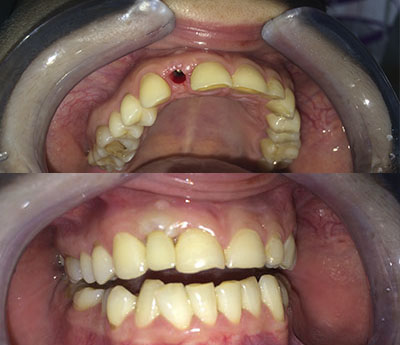

Implantul dentar este un dispozitiv confecționat din titan, care are rolul de a înlocui absența unuia sau mai multor dinți. Implantul îndeplinește funcția de radacină pentru viitoarea coroană dentară. Este fixat după intervențiile pregătitoare.